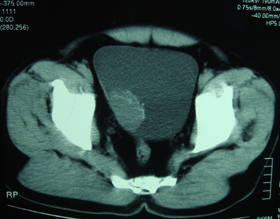

标题: CT28320:典型病例,男,56岁。无痛性血尿3月。 [打印本页]

典型病例,男,56岁。无痛性血尿3月。

膀胱占位性病变,呈菜花状生长,考虑膀胱癌。 期待病理。